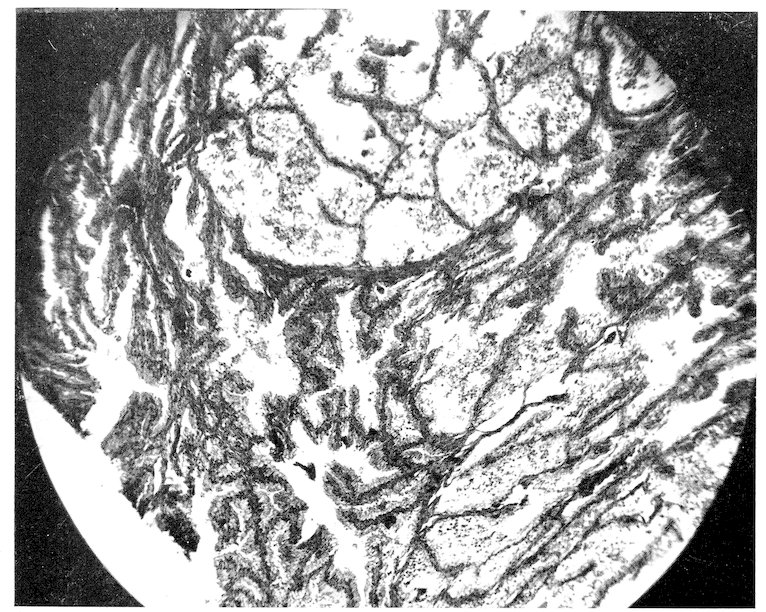

Some attention has been given to the study of diets for the wild specimens of our Garden, but no systematic observations have been made or records kept upon purely physiological subjects. Reference will be made at appropriate places to accepted comparative physiological facts, but our statistics permit additions to such knowledge only in a limited manner and in isolated instances. Doctor Corson-White has very ably summarized the diet, alimentary tract and physiology of the zoological groups with the pathology as found in our records.

A word might be added here as to the destruction of animals by injury from fighting and harassment by others in the cage. Fighting doubtless causes death, especially when males are together, but it is our experience that in cases of traumatic death search should always be made to see if the resistance of the dead animal had not been reduced by some disease. This is well illustrated in birds. Very frequently a specimen will come to autopsy with its head feathers plucked out, or with a billthrust in the wing or pelvic region. Such birds are not infrequently suffering from malaria, or heavy intestinal parasitism or from organic disease whereby the resistance and self-preservatory power has been decreased.

The foregoing survey of the approach to our subject reveals the multiplicity of factors which affect the study of comparative pathology. No one of them can be entirely omitted, no one is without some effect upon the origin and expression of disease, and no one is fully understood. Yet it is to be hoped that a study of our material, accumulated under routine conditions and uninfluenced by any experimental procedures, will demonstrate the natural response of various zoological groups to morbific agencies. Perhaps reactively some of the modifying 41conditions may thus be understood. It is also not unreasonable to expect that alterations observed as natural responses in a large number of specimens in nearly normal surroundings would serve as more reliable guides to investigative speculation than would changes in a few animals under artificial technical experimentation. We hope that the few facts we have been able to record may afford someone a basis for further biological studies. It is also to be hoped that something has been learned which in the end will afford an explanation of the diseases of man. Too great optimism in this direction should be guarded against because the human being is indeed an animal sui generis and, from the standpoint of normal conditions of nature, a wild animal.

The zoological classification found on pages 43–46 was compiled in 1903 by Dr. A. E. Brown on the basis of the British System. With a few exceptions the computations in the text are made on the basis of zoological orders since the number of specimens in families is often too small and the complications of so many different figures would be confusing. The tables will be found to correspond to the sequence of the classification. Dr. Corson-White has, however, used for her analysis the dietary groupings. A carnivore in her chapter implies strictly a meat-eater, in the rest of the book one of the zoological group Carnivora.